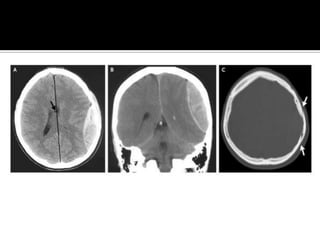

Masc ebrio de 18 a., fue asaltado con una botella de vidrio en la región parietal izquierda de la

región temporoparietal izquierda. La TC reveló un hematoma epidural de 2.5 cm en la región

parietal izquierda (grupos A y B) que subyace a una fractura lineal, no desplazada del cráneo

(Grupo C, flechas). Presento efecto de masa, ensanchamiento del sistema ventricular izquierda, y

6 mm de desplazamiento de línea media de izquierda a derecha (panel A, flecha). Después de 30